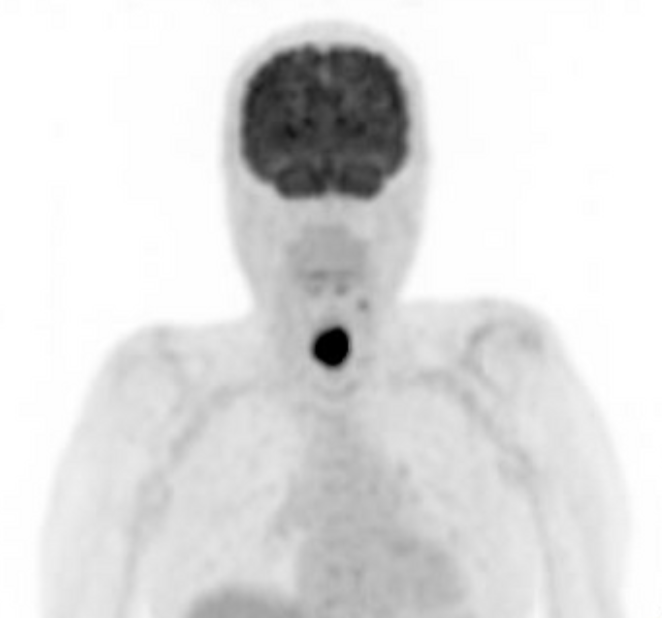

Positron emission tomography (PET) typically involves injecting a radioactive sugar solution (FDG) into your veins, which is absorbed by cancer cells because they are actively using sugar metabolism to grow. Other normal organs such as the brain will light up because those cells also preferentially use sugar for its energy source. After some time to allow the sugar to be taken up, you will be scanned in a combined PET and CT scanner. The low level radiation from FDG will be detected by the scanner and overlaid on the CT scan. This scan is useful because it is more sensitive than a CT scan for detecting cancer metastasis/spread.